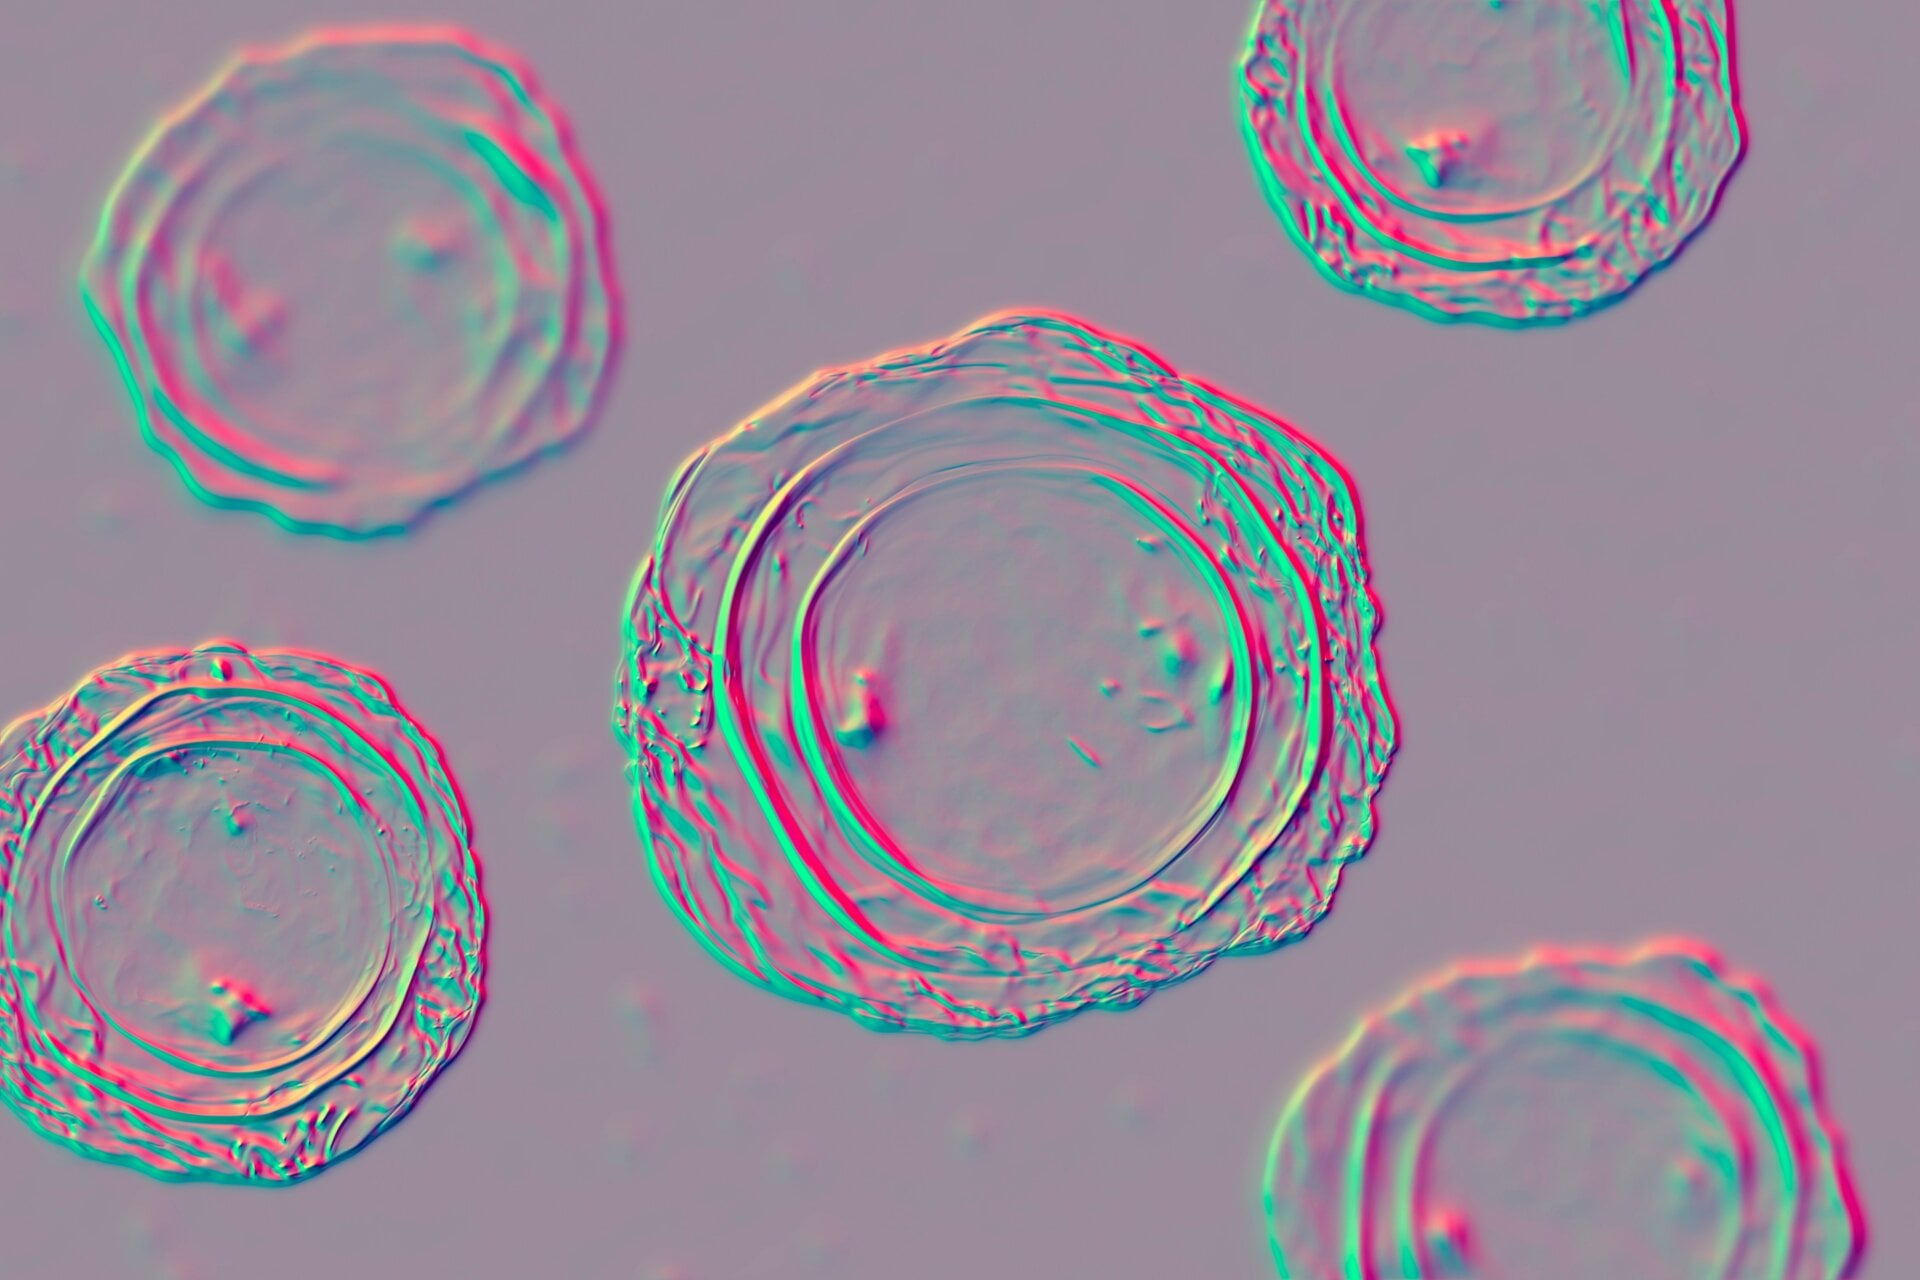

Ascaris

These guys are another type of roundworm you can catch from the beach or the soil more generally. Ascaris infections are actually the most common soil-transmitted parasites in humans, with up to a billion people worldwide currently thought to carry them. People will usually catch these worms from ingesting or touching soil or water contaminated by another person’s infected feces. Thankfully, Ascaris infections are relatively uncommon in the U.S.